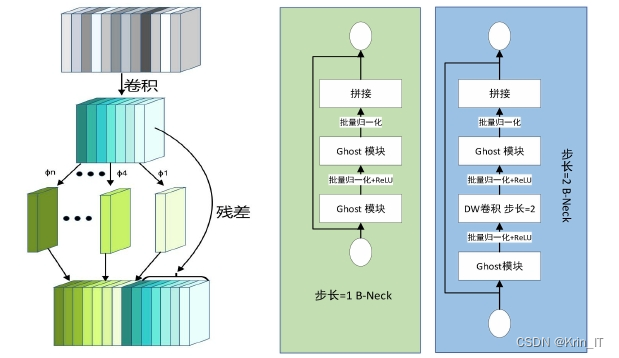

GhostNet主要由Ghost模块构成,该模块通过独特的设计实现了高效和灵活的特征提取。Ghost模块中的主卷积可以具有定制的内核大小,首先生成一些固有的特征映射。这些特征映射随后通过普通的线性运算进行增强,增加了通道的多样性。这种设计使得Ghost模块能够在保持低计算复杂度的同时,有效提取和保留关键特征信息。此外,Ghost模块中的特征映射与线性变换能够并行处理,从而确保了固有特征的保留。

Ghost模块的特殊结构能够通过廉价的操作生成丰富的重影特征映射,这些映射详细揭示了内在特征背后的信息。其灵活的特性使得Ghost模块可以作为即插即用的组件,能够轻松地升级现有的卷积神经网络,提升其性能。考虑到Ghost模块的优良性能,研究中在改进YOLOv5时采用了该模块,以进一步提升目标检测的准确性和效率。通过Ghost模块的引入,网络模型能够在保持轻量化的同时,获得更为丰富的特征表示,推动了深度学习在计算机视觉领域的应用发展。

在主干网络的改进方面,原版YOLOv5的主干网络部分大体保留了YOLOv4的结构,但CSPDarknet53由于参数量庞大,对计算机的存储和计算能力要求较高,进而影响了运行速度。为了解决这一问题,研究参考了Ghost bottleneck结构,对其进行了改进。新的Ghost bottleneck结构中引入了前述的时空注意力机制,尽管增加了部分参数,但这一机制是为了适应肺部CT影像中可能出现的多种肺结节而专门设计的,从而能够更准确地提取特征信息。尽管整体计算量有所增加,但相较于YOLOv5原有的CSPDarknet53结构,其计算复杂度仍然显著降低。改进后的Ghost bottleneck结构(简称G-BNeck)通过增强特征提取能力,进一步提升了模型在复杂任务中的表现。

以YOLOv5的主体结构为基础,首先将骨干网络部分更改为改进的Ghost bottleneck(G-Bneck)结构,这一改动使得网络更加轻量化,提升了运行效率。随后,在G-Bneck中引入了时空注意力机制,以减少冗余信息对识别效果的影响,增强了模型对关键特征的关注能力。结合SPP结构与FPN(特征金字塔网络)和PAN(路径聚合网络),构建了一个特征深度融合提取网络,实现对目标特征的详尽提取。最终,通过这一改进的网络结构输出预测结果,完成了算法的构建任务。